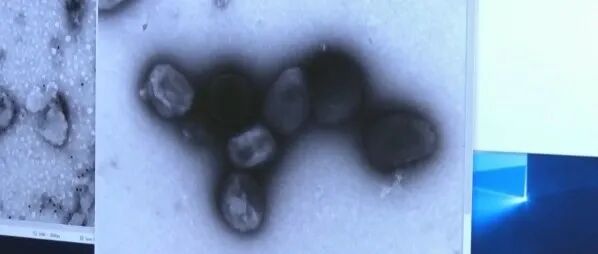

刚刚!新冠之外,中国要求入境人员排查两种病毒!加拿大比较严重......

若在国外有过接触史和暴露史,尚未出现症状,可主动联系当地疾控中心进行咨询和报备。